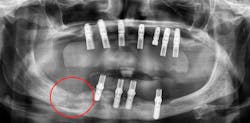

In addition to patient-related factors, a site-specific negative effect on bone healing has also been suggested. Sites of previous implant or graft failure will have compromised alveolar bone quality and quantity compared with unoperated sites. Thus, significantly lower survival rates of implants placed in sites of previous failure have been reported compared to initial implants, supporting evidence of site factors for failures.5 This site-specific theory is further supported by the finding that failed implants are often found in patients who have also had successful implants placed at other sites (figures 5a–5c).

Figures 5a–5c: Successive implant failures and bone augmentation in the right posterior mandible, resulting in compromised bone healing and subsequent chronic osteomyelitis.